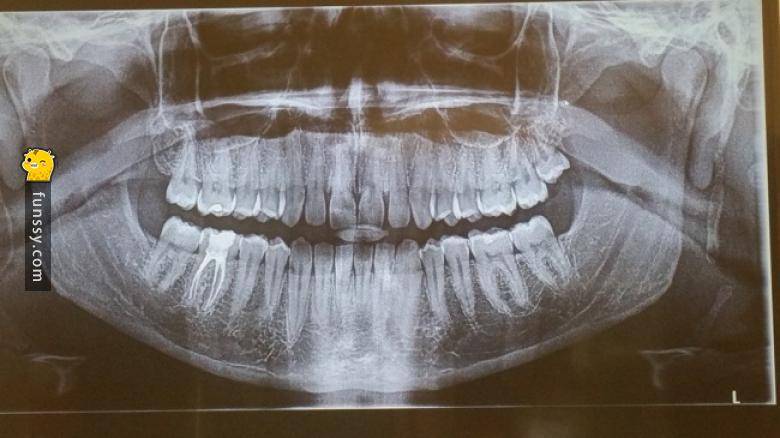

#1 沒有智齒

只有大概20%的人有這種癥狀。